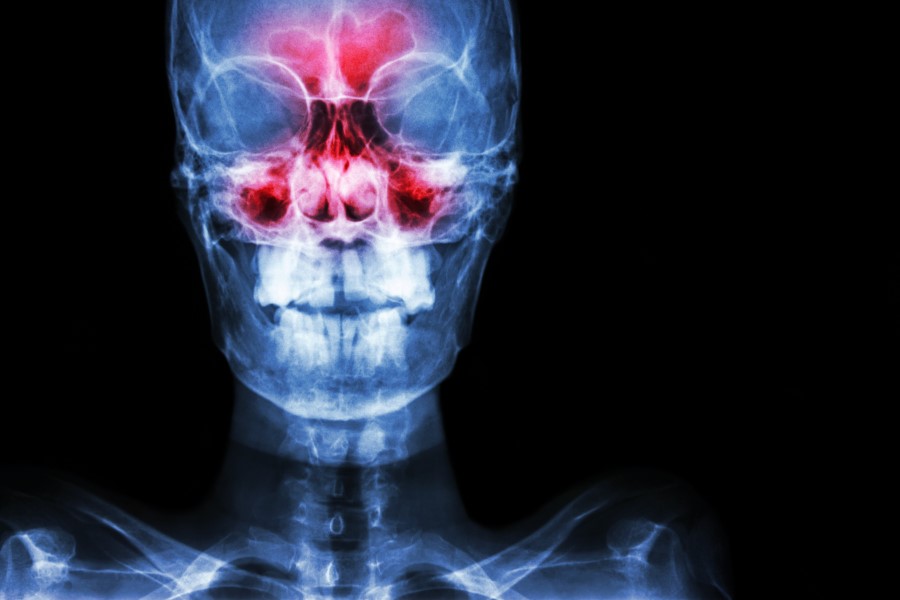

Rentgen (RTG) zatok – jak przebiega i jak się przygotować? Kiedy wykonać rentgen zatok?

Badanie rentgenowskie jest jednym z podstawowych badań wykorzystywanych w medycynie. Choć najczęstszymi przyczynami wykonania RTG są wskazania ortopedyczne (np. podejrzenie złamania), to rentgen sprawdza się również w przypadku diagnostyki stanu zapalnego, m.in. zatok. Jest to jedno z najlepiej dostępnych, szybkich i niedrogich badań diagnostycznych. Jak wygląda rentgen zatok? W jaki sposób należy przygotować się do badania?

W sezonie jesienno-zimowym jesteśmy szczególnie podatni na różnego rodzaju infekcje. Tak jest też w przypadku zapalenia zatok, które najczęściej atakuje w chłodniejsze miesiące, kiedy temperatura powietrza na zewnątrz i w pomieszczeniu znacząco się różni, a poprzez działające ogrzewanie, powietrze w mieszkaniu jest suche. Warunki sprzyjają wówczas przesuszaniu błony śluzowej nosa i zatok, a to prowadzi do utrudnionej wentylacji i podatności na atak drobnoustrojów (wirusów i bakterii). Na zdjęciu rentgenowskim podczas zapalenia zatok widoczny jest płyn w przestrzeniach zatokowych. Zapalenie zatok częściej atakuje osoby z tendencją do nieżytu nosa (np. poprzez krzywą przegrodę nosową czy obecność polipów).

Badanie RTG zatok daje wyraźny obraz tego, co się w nich dzieje. Lekarz może na jego podstawie ocenić m.in. obecność płynu w zatokach, polipów, torbieli, zgrubienia błony śluzowej, torbieli oraz ropni okołozębowych.